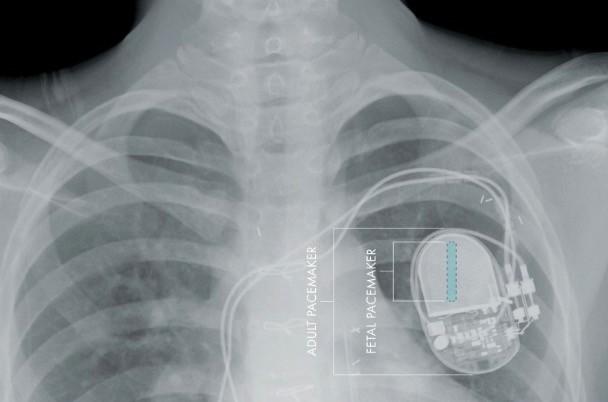

在美国,上万人被要求更新他们的心脏起搏器。据外媒securityaffairs报道,美国食品和药物管理局(FDA)正在召回大约50万个起搏器,因为它们很容易受到黑客的攻击。

黑客利用漏洞重新编程,可以停止心脏起搏器电池的运作或者修改心脏跳动的方案,在发现这个漏洞后,FDA已召回465000心脏起搏器。

受影响六种心脏起搏器是来自Abbott公司的,分别是Accent, Anthem, Accent MRI, Accent ST, Assurity和 Allure.